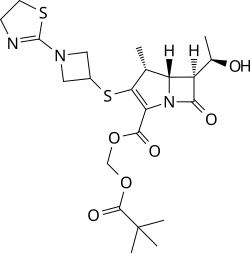

| Formula | C22H31N3O6S2 |

| 3D model (JSmol) | |

Tebipenem (brand name Orapenem) is a broad-spectrum orally-administered antibiotic, from the carbapenem subgroup of β-lactam antibiotics. It was developed as a replacement drug to combat bacteria that had acquired antibiotic resistance to commonly used antibiotics.[1][2] Tebipenem is formulated as the ester tebipenem pivoxil due to the better absorption and improved bioavailability of this form.[3] It has performed well in clinical trials for ear infection and looks likely to be further developed in future.[4] It is only marketed in Japan.[5] Tebipenem is the first carbapenem whose prodrug form, the pivalyl ester, is orally available.[6]